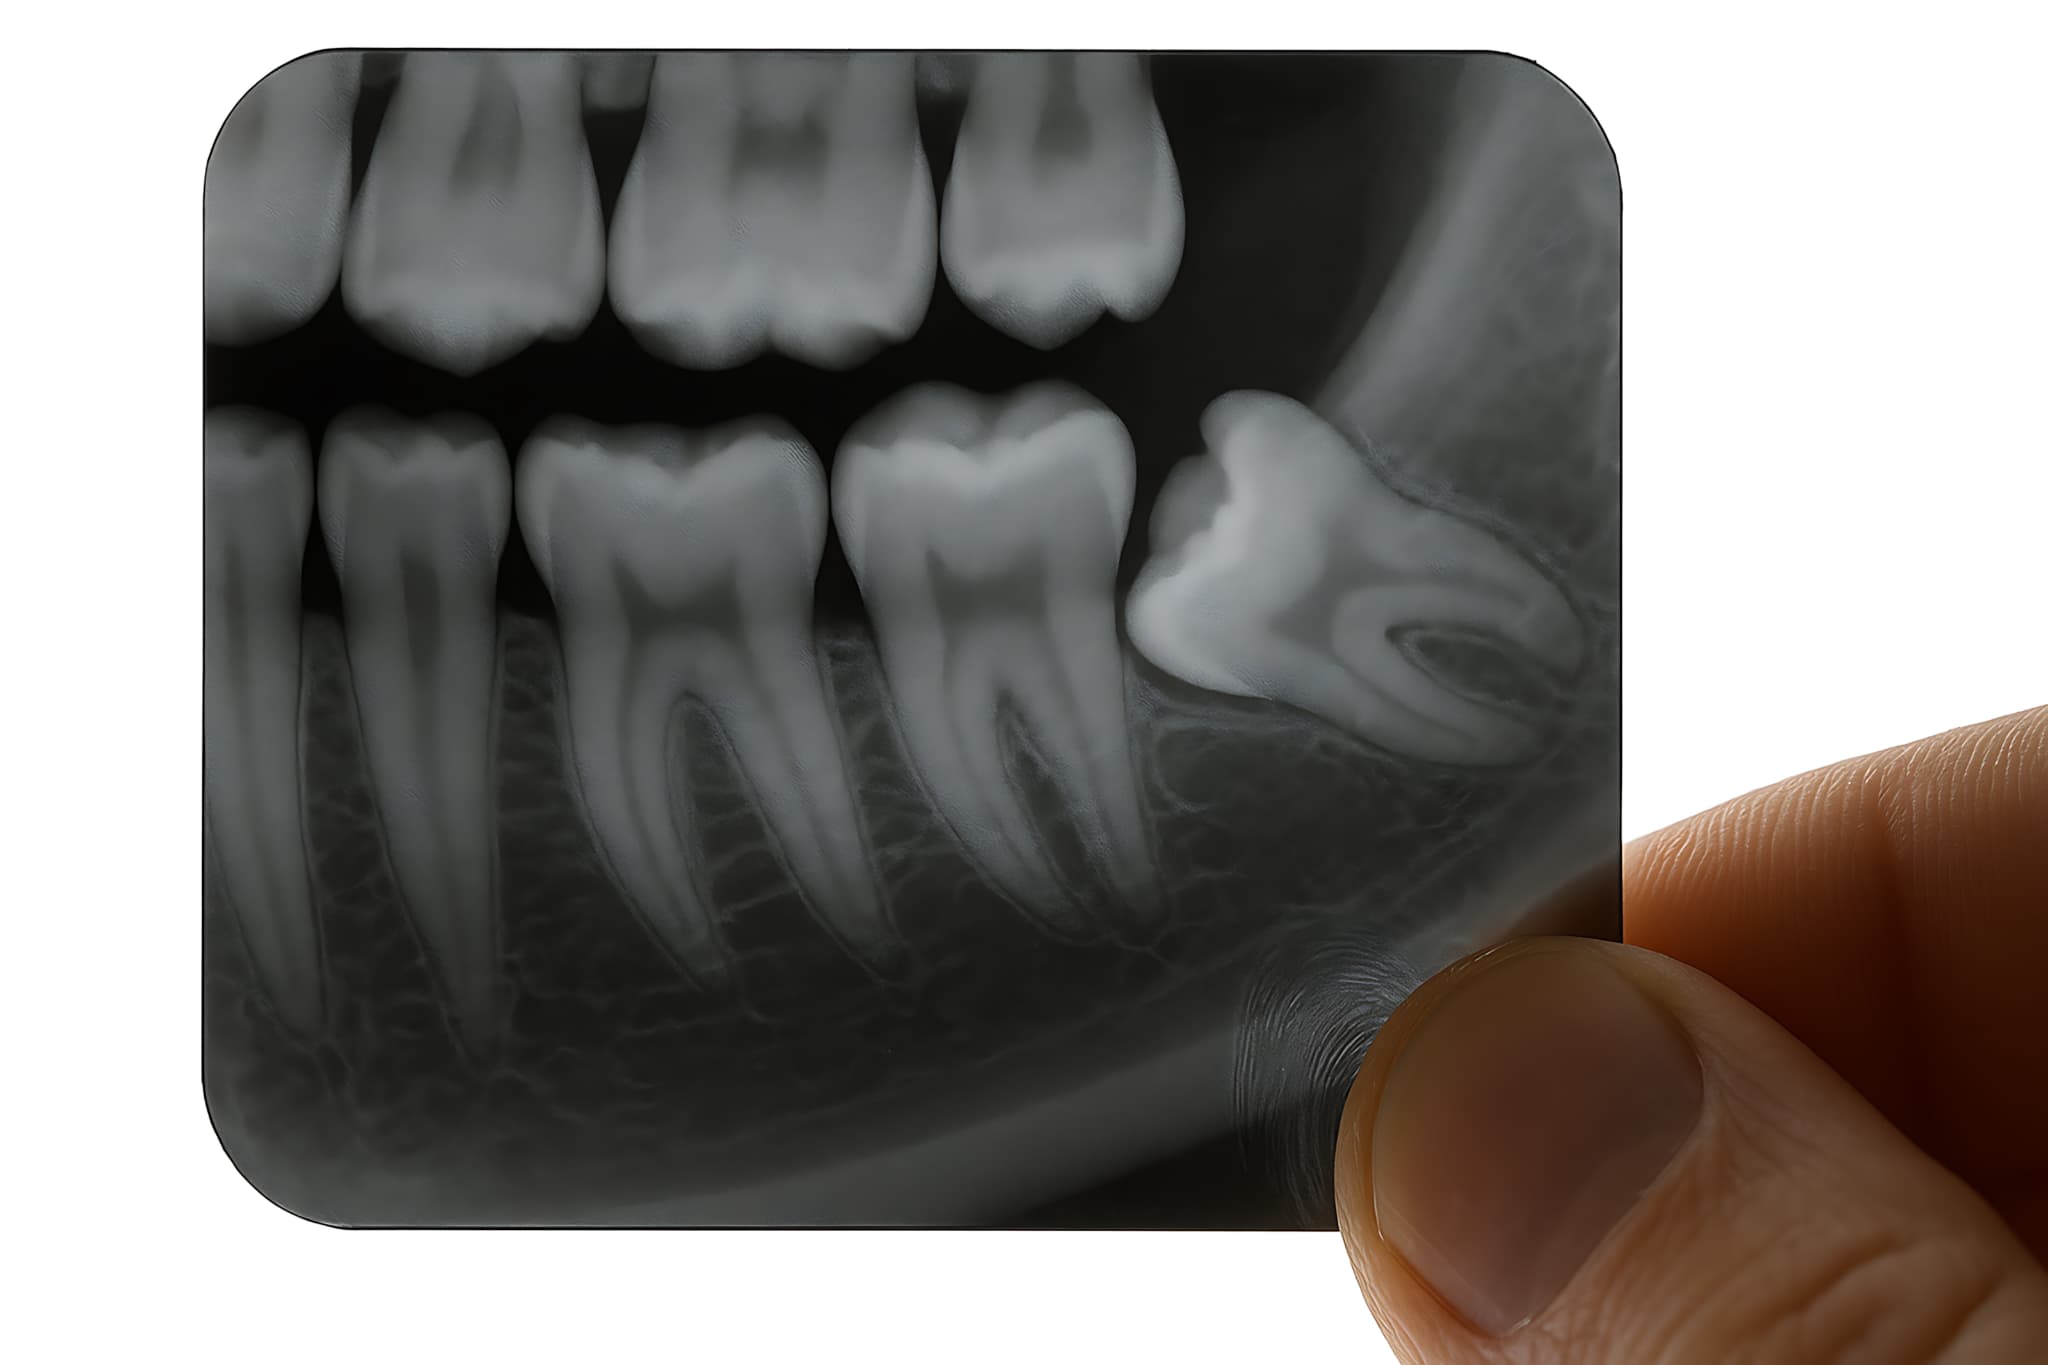

あごの骨の中で親知らずの向きや位置がずれていると、斜めや横向きに生えたり、歯ぐきから一部だけ見えている半埋伏の状態になったり、完全に骨の中に埋まったままの完全埋伏になったりします。

あごの骨の中で親知らずの向きがずれていると、斜めや横向きに生えてきたり、途中で止まってしまったりします。まっすぐ生えるスペースが足りないため、手前の奥歯を強く押したり、歯ぐきを内側から突き上げたりして、鈍い痛みや圧迫感が出ます。

下の親知らずは特に、あごの骨が細くてスペースが不足しやすく、歯ぐきの一部だけを破って生えてくることがあります。このような半埋伏の状態では、歯ぐきが繰り返し傷つき、炎症や腫れを起こしやすくなります。

あごの骨の中で親知らずの根が神経の近くまで伸びている場合には、レントゲンや必要に応じてCT撮影を行い、神経との位置関係を確認したうえで、抜歯の可否や方法を慎重に検討します。

親知らずの位置や向き、根の形や神経との位置関係を詳しく知るために、レントゲン撮影を行うことが一般的です。

必要に応じて、三次元的に確認できるCT撮影を行う場合もあります。これらの情報をもとに、痛みの原因を特定し、治療方針を決めていきます。